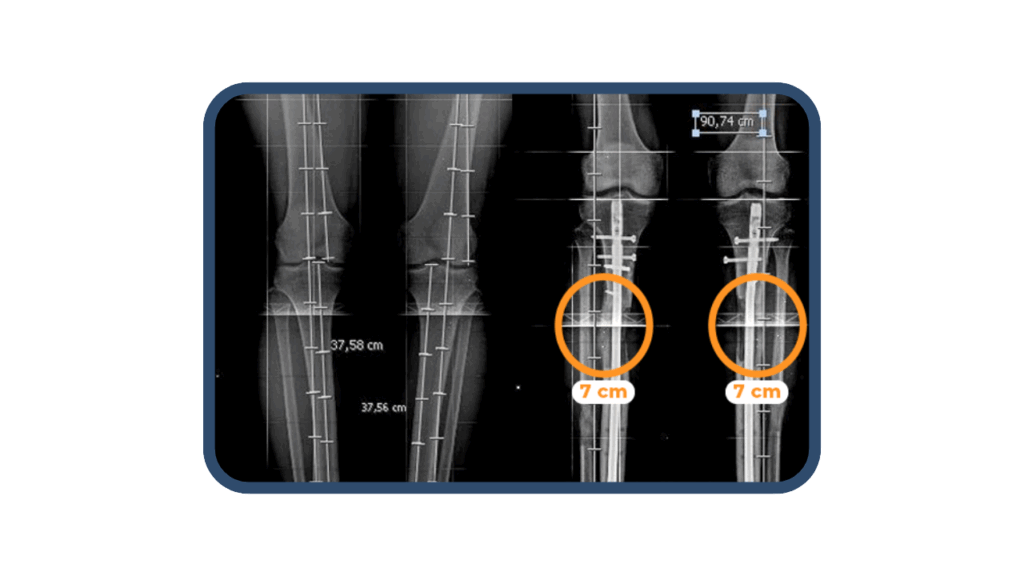

En las consultas especializadas en alargamiento óseo, el Dr. Christian Huamaní explica detalladamente el proceso de elongación de fémures y tibias. La consulta es complementada con la telerradiografía realizada a los pacientes, la cual es fundamental para conocer y explicar a los pacientes acerca de la cantidad (centímetros) que pueden elongar sus articulaciones.

En la cirugía de alargamiento óseo se realiza el método LON, el cual permite reducir el tiempo de permanencia del fijador externo (HMC). El procedimiento consiste en realizar una fractura controlada en el hueso (fémur o tibia). Luego, se coloca un clavo endomedular dentro del hueso , junto al fijador externo HMC que es unido a la extremidad, gracias a agujas percutáneas llamados Schantz. Nuestra cirugía de alargamiento óseo, suele durar 2 horas aproximadamente. La hospitalización alrededor de 5 días, para seguidamente continuar con el plan de recuperación preparado por Arthrosalud.